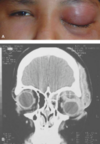

Exoftalmos

Sintomas de oftalmopatía tiroidea

Exoftalmos, restricción de los movimientos, edema. lagrimeo, hiperemia, fotofobia y dolor

Sintomas de seudotumor agudo

Síntomas de seudotumor agudo